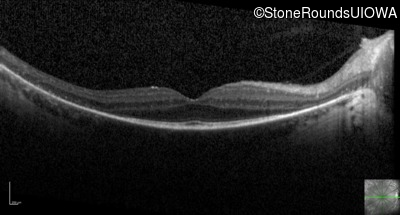

Optical Coherence Tomography - Right - 20/25 -1

Exemplar / OCT Stack

OCT Stack